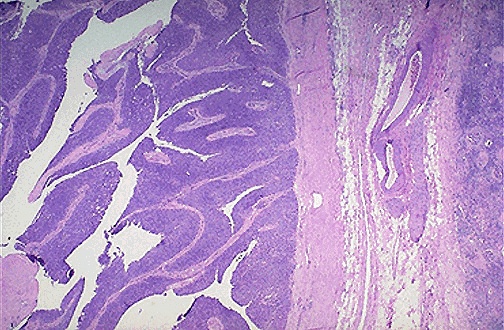

| A urothelial carcinoma of the urothelium is shown here at low power to reveal the frond-like papillary projections to the left of the tumor above the surface. It is differentiated enough to resemble urothelium, but it is producing a mass effect. No invasion to the right is seen at this point. |